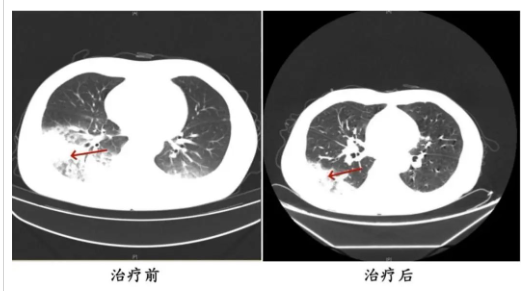

李先生肺部治療前與治療后的對比

起初,他以為是吹空調(diào)吹感冒了,于是自行服用感冒藥,但病情并未好轉(zhuǎn),反而愈發(fā)嚴(yán)重。家人見狀,立即將他送往成都市第五人民醫(yī)院感染性疾病科。胸部CT顯示李先生的左肺已出現(xiàn)大面積白色影像,幾乎占據(jù)一半肺部。經(jīng)過肺泡灌洗NGS檢測,最終確認(rèn)“罪魁禍?zhǔn)住笔鞘确诬妶F(tuán)菌。